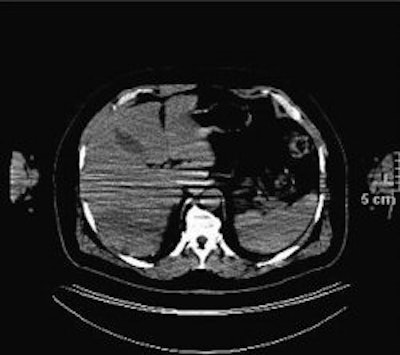

![]() |

| The image shows a patient with lymphoma and nodules in terminal ileum (arrow). The nodules are not apparent on PET/CT without benefit of oral contrast. The finding is clinically significant, because it could represent extranodal spread of lymphoma. It proved to be Crohn's disease after colonoscopy and surgical removal. "Limitations of CT during PET/CT" (Journal of Nuclear Medicine, Vol. 48:10, pp. 1583-1591). Reprinted by permission of SNM. |